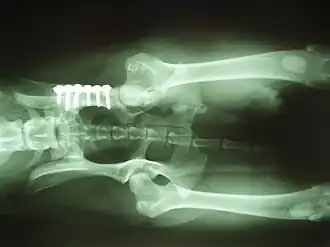

- Het kantelen van de heupkom over de heupkop. De heupkom wordt op meerdere plaatsen doorgezaagd, gekanteld totdat de heupkop goed in de heupkom past, en weer vastgezet met metalen schroeven. Hierdoor ontstaat er een betere aansluiting. Deze operatie wordt uitgevoerd bij jonge honden (ouder dan 8 maanden) met losse heupen zonder vormverandering.